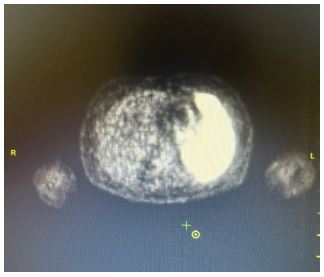

A 57-year-old male patient presented to the internal medicine outpatient clinic with complaints of weight loss, anorexia and early satiety that had lasted for a period of two months. The patient had been diagnosed with prostate carcinoma and was undergoing Gonadotropin-Releasing Hormone (GnRH) agonist treatment. On physical examination, the patient was conscious, orientated. The patient appeared pale and weak. The patient’s vital signs revealed a blood pressure of 90/60 mmHg, a pulse rate of 114 beats per minute, and an oxygen saturation level of 98%. Abdominal examination revealed tenderness in the gastric region, while additional examination findings were unremarkable. Laboratory analysis revealed the following results: haemoglobin 6.8 g/dL, haemotocrit 25.6%, MCH 15.8 pg and MCV 69.6 fL. Biochemical parameters were found to be within normal limits. Serum ferritin levels were found to be 10 μg/L, while vitamin B12 levels were recorded at 216 ng/L. Furthermore, coagulation tests, acute phase reactants, hepatitis and HIV markers were found to be negative. Direct Coombs, LDH, and Haptoglobin levels were found to be within normal parameters. A peripheral smear revealed no signs of pathological cells, but did indicate iron deficiency anaemia. The patient was evaluated for gastrointestinal bleeding, but no such bleeding was detected. The patient was admitted to the internal medicine ward on the basis of anaemia and oral intake disorder, and treatment was initiated. Abdominal ultrasonography revealed no abnormalities. An upper gastric endoscopy was performed to investigate the aetiology of the anaemia, revealing an ulcerated area in the large curvature region of the gastric corpus. Consequently, a biopsy was taken from this area, and the following stains were found to be diffusely positive: CD45(LCA) (Clone Roche RP2-18), MUM-1, PAX-5, CD20 (Clone Roche L26), CD79a, Bcl-6. In addition, 40% staining with C-myc was observed. Conversely, staining for CyclinD1 (Clone Roche SP4-R), Pankeratin, CD30, CD23 (Clone Roche SP23), ALK, CD10 (Clone Roche SP67) was negative. Non-neoplastic T lymphocytes were stained with CD3 (Clone Roche 2GV6) and CD5. The proliferation index with Ki-67 is 95%. Conversely, EBER staining, utilised in conjunction with the chromogenic in situ hybridisation method, yielded a negative result. Furthermore, both the TdT stain and the Helicobacter pylori stain returned negative results. The histopathological findings observed in the sections prepared from the gastric corpus marked material, in conjunction with the results of immunohistochemical staining, allowed for the diagnosis of aggressive large B-cell non-Hodgkin’s lymphoma. Positron Emission Tomography-Computed Tomography (PET-CT) was performed for lymphoma staging, revealing involvement in all lymph nodes and the spleen, consistent with lymphoma (Figure 1). R-CHOP regimen chemotherapy was initiated as a treatment.No involvement was detected in the control PET-CT of the patient whose chemotherapy treatment had concluded (Figure 2).

Figure 1: PET-CT; Axial section showing uptake of hypermetabolic activity in the spleen.

Figure 2: PET-CT; Axial section showing no uptake of hypermetabolic activity in the spleen after chemotherapy.